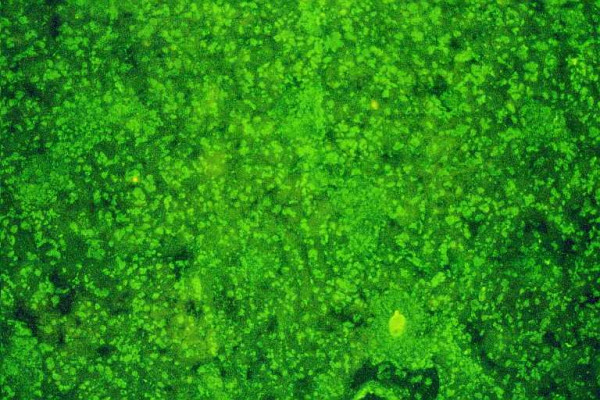

自身免疫性肝炎(AIH)是一种慢性肝脏坏死性炎症疾病,其特征是高丙种球蛋白血症、特征性自身抗体、与 HLA DR3 或 DR4 相关以及对免疫抑制治疗的良好反应。病因不明。在没有病毒、代谢、遗传和中毒性慢性肝炎或肝损伤病因的情况下,检测非器官和肝脏相关的自身抗体仍然是诊断该病的标志。本文报告了 AIH 目前的分类以及在该疾病中发现的几种自身抗体/目标自身抗原。此外,还阐述了这些标记物在鉴别诊断和 AIH 发病机制研究中的重要性。AIH 可细分为两大类型:AIH 1 型(AIH-1)和 AIH 2 型(AIH-2)。AIH-1 型的特征是检测到平滑肌自身抗体(SMA)和/或抗核抗体(ANA)。检测抗中性粒细胞胞浆自身抗体(ANCA)、抗淀粉样糖蛋白受体抗体(抗ASGP-R)和抗可溶性肝抗原或肝胰腺抗体(抗SLA/LP)可能有助于鉴别ANA/SMA血清阴性的患者。AIH-2的特点是存在针对肝脏和肾脏微粒体抗原的特异性自身抗体(抗LKM-1型或不常见的抗LKM-3型)和/或针对肝脏胞浆1抗原的自身抗体(抗LC1)。在一些慢性丙型肝炎(HCV)和慢性丁型肝炎(HDV)患者中也能检测到抗 LKM-1 和抗 LKM-3 自身抗体。细胞色素 P450 2D6 (CYP2D6) 已被证实是 AIH-2 和 HCV 感染中抗 LKM-1 自身抗体的主要靶抗原。最近有令人信服的数据表明,CYP2D6 在肝细胞表面的表达表明,抗 LKM-1 自身抗体在肝损伤中起着致病作用。UDP-糖醛酸转移酶家族 1 已被确定为抗 LKM-3 的靶自身抗原。因此,区分 AIH 和慢性病毒性肝炎(尤其是 HCV)尤为重要。最近,抗SLA/LP和抗LC1自身抗体的分子靶点被确定为一种50 kDa的UGA抑制tRNA相关蛋白和一种肝脏特异性酶--甲氨蝶呤环化酶。抗ASGP-R和抗LC1自身抗体似乎与疾病的严重程度和对治疗的反应密切相关,这表明这些自身抗体对肝细胞损伤具有致病作用。但一般来说,自身抗体不应被用于监测治疗、预测 AIH 的活动性或预后。最后,本文还介绍了一种特殊形式的 AIH,即自身免疫性多内分泌病-念珠菌病-外胚层营养不良综合征(APECED),它可能发生在一些患有罕见遗传综合征的患者身上。肝微粒体自身抗体(抗-LM)是在作为 APECED 疾病组成部分的 AIH 中检测到的特异性自身抗体,也可在二氢嗪诱发的肝炎病例中检测到。在与 APECED 相关的 AIH 和二氢嗪诱导的肝炎中,细胞色素 P450 1A2 被确定为抗 LM 自身抗体的靶自身抗原。后者可能表明,类似的自身免疫致病机制可导致易感个体的肝损伤,而与原发性缺陷无关。自身抗原-自身抗体复合物的特征描述仍然是一种极具吸引力的重要工具,可用于获得正确的诊断,并深入了解肝脏耐受性是如何被放弃以及 AIH 是如何产生的这一尚未解开的谜团。

Autoimmune hepatitis (AIH) is a chronic necroinflammatory disease of the liver characterized by hypergammaglobulinemia, characteristic autoantibodies, association with HLA DR3 or DR4 and a favorable response to immunosuppressive treatment. The etiology is unknown. The detection of non-organ and liver-related autoantibodies remains the hallmark for the diagnosis of the disease in the absence of viral, metabolic, genetic, and toxic etiology of chronic hepatitis or hepatic injury. The current classification of AIH and the several autoantibodies/target-autoantigens found in this disease are reported. Current aspects on the significance of these markers in the differential diagnosis and the study of pathogenesis of AIH are also stated. AIH is subdivided into two major types; AIH type 1 (AIH-1) and type 2 (AIH-2). AIH-1 is characterized by the detection of smooth muscle autoantibodies (SMA) and/or antinuclear antibodies (ANA). Determination of antineutrophil cytoplasmic autoantibodies (ANCA), antibodies against the asialoglycoprotein receptor (anti-ASGP-R) and antibodies against to soluble liver antigens or liver-pancreas (anti-SLA/LP) may be useful for the identification of patients who are seronegative for ANA/SMA. AIH-2 is characterized by the presence of specific autoantibodies against liver and kidney microsomal antigens (anti-LKM type 1 or infrequently anti-LKM type 3) and/or autoantibodies against liver cytosol 1 antigen (anti-LC1). Anti-LKM-1 and anti-LKM-3 autoantibodies are also detected in some patients with chronic hepatitis C (HCV) and chronic hepatitis D (HDV). Cytochrome P450 2D6 (CYP2D6) has been documented as the major target-autoantigen of anti-LKM-1 autoantibodies in both AIH-2 and HCV infection. Recent convincing data demonstrated the expression of CYP2D6 on the surface of hepatocytes suggesting a pathogenetic role of anti-LKM-1 autoantibodies for the liver damage. Family 1 of UDP-glycuronosyltransferases has been identified as the target-autoantigen of anti-LKM-3. For these reasons the distinction between AIH and chronic viral hepatitis (especially of HCV) is of particular importance. Recently, the molecular target of anti-SLA/LP and anti-LC1 autoantibodies were identified as a 50 kDa UGA-suppressor tRNA-associated protein and a liver specific enzyme, the formiminotransferase cyclodeaminase, respectively. Anti-ASGP-R and anti-LC1 autoantibodies appear to correlate closely with disease severity and response to treatment suggesting a pathogenetic role of these autoantibodies for the hepatocellular injury. In general however, autoantibodies should not be used to monitor treatment, predict AIH activity or outcome. Finally, the current aspects on a specific form of AIH that may develop in some patients with a rare genetic syndrome, the autoimmune polyendocrinopathy-candidiasis-ectodermal dystrophy syndrome (APECED) are also given. Autoantibodies against liver microsomes (anti-LM) are the specific autoantibodies detected in AIH as a disease component of APECED but also in cases of dihydralazine-induced hepatitis. Cytochrome P450 1A2 has been identified as the target-autoantigen of anti-LM autoantibodies in both APECED-related AIH and dihydralazine-induced hepatitis. The latter may indicate that similar autoimmune pathogenetic mechanisms can lead to liver injury in susceptible individuals irrespective of the primary defect. Characterization of the autoantigen-autoantibody repertoire continues to be an attractive and important tool to get access to the correct diagnosis and to gain insight into the as yet unresolved mystery of how hepatic tolerance is given up and AIH ensues.